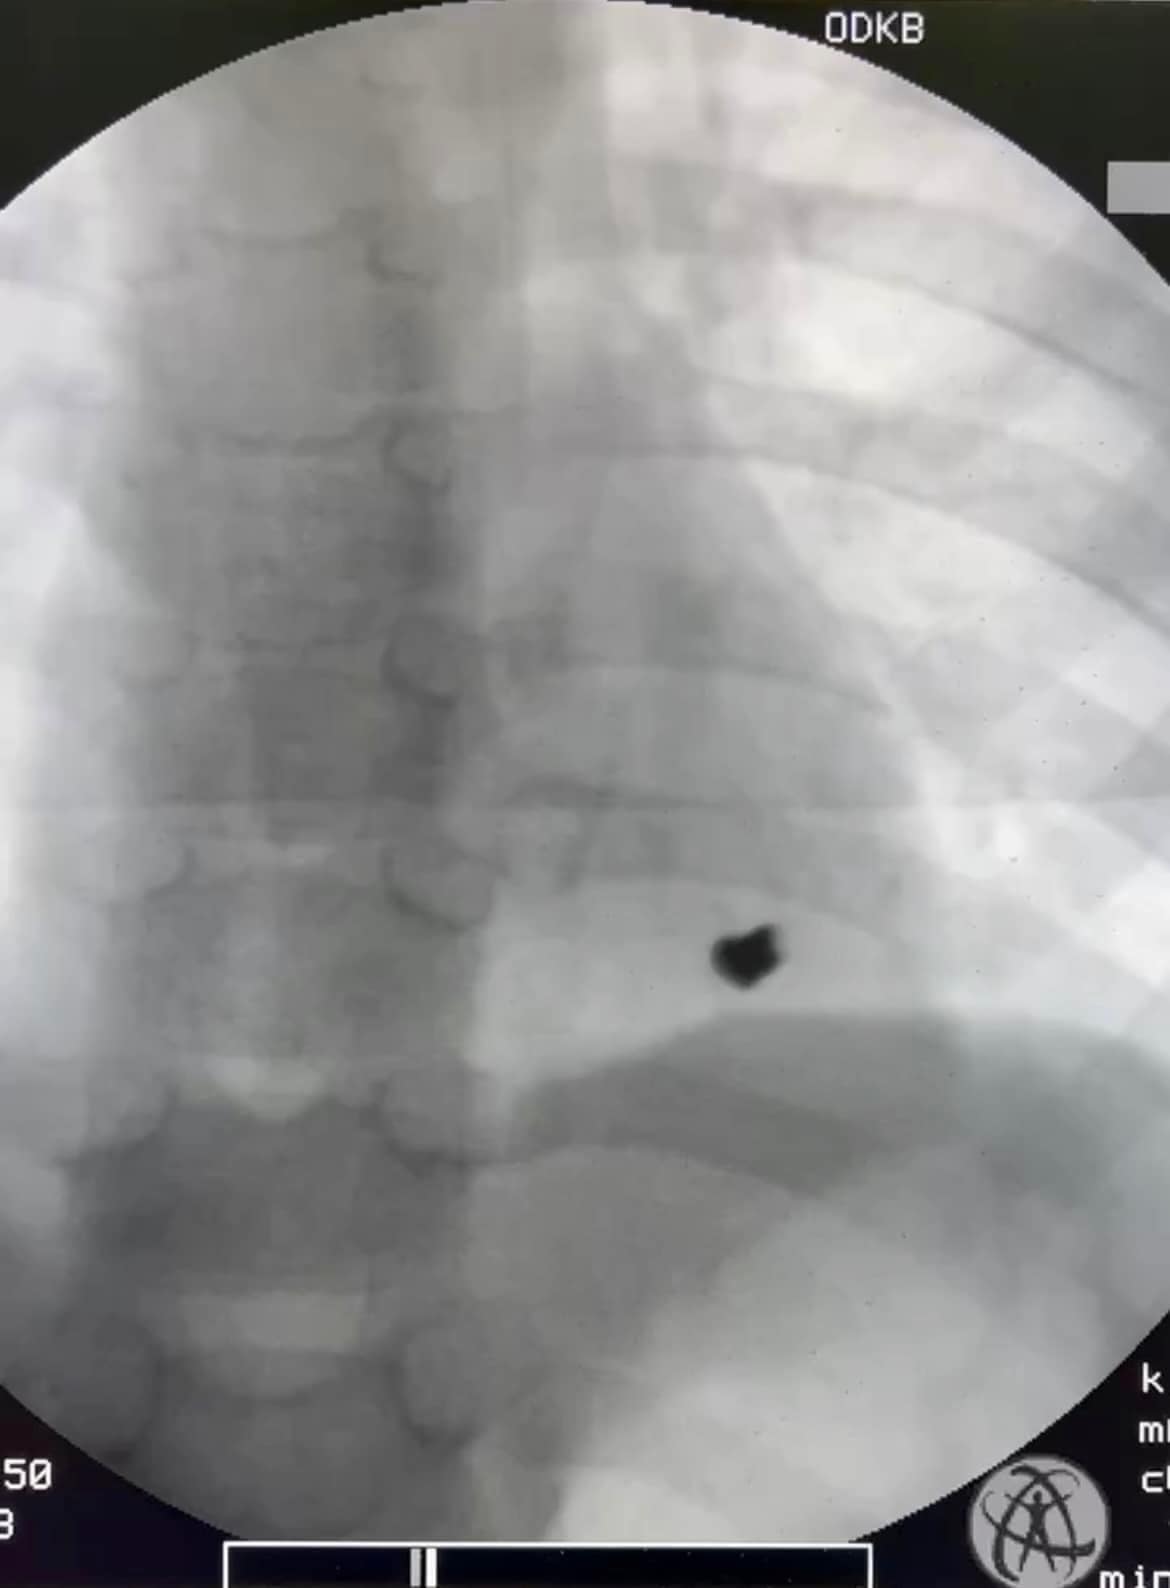

1 апреля в медицинское учреждение был госпитализирован 7-летний ребенок с травмой сердца от пулевого ранения. В больнице отметили, что игра двух братьев 7-ми и 8-ми лет с винтовкой, которая, как потом выяснилось, была заряжена, закончилась ранением левой части грудной стенки с проникновением пули в полость перикарда (сердечной сумки) и поражением задней стенки левого желудочку сердца.

«Ребенок родился в «рубашке», потому что, к счастью, мальчик был вовремя госпитализирован в Татарбунарскую многопрофильную больницу и переведен в Одесскую детскую областную больницу, где был прооперирован в ургентном порядке кардиохирургами – заведующим отделением сердечно-сосудистой хирургии Владимиром Бузовским и врачом Гоцуляком. Они выполнили оперативное вмешательство на сердце и спасли ребенка, – сообщил директор Одесской областной детской клинической больницы Павел Георгиев.